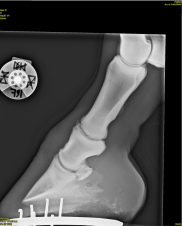

Du modtager to røntgenbilleder fra en kollega, der er blevet kaldt ud til en hest med et indtrådt fremmedlegeme. Din kollega er i tvivl om, hvilken anatomisk struktur, der kan være blevet skadet af fremmedlegemet. Kan du hjælpe?

1 Den elastiske ballepude

2 Hovleddet

3 Den distale seneskede

4 Bursa podotrochlearis

Det rigtige svar er 4